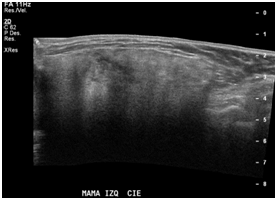

A 47year-old woman with history of a long standing palpable mass on the left breast, which was biopsied on 2006 resulting in hamartoma. She had first degree familiar history of breast cancer with her mother diagnosed younger than 50 \years of age and who later on died of that cause. The patient presented to our office, in June 2016 for progressive growth of her breast tumour. At examination her breasts were fibrous, with a palpable firm and mobile breast mass, not fixed to skin, of 8x6x5cm on the left LIQ, and another large, soft and well defined mass in left LOQ and UOQ of 10x10x5cm, There were no palpable masses in the axilla. On mammography there was a radiolucid well defined breast mass in the left LOQ and UOQ, which was stable in size and shape regarding prior mammogram of twoyears. A new dense, oval and partially defined breast mass was evident in the LIQ (Figure 1). The latter on breast ultrasound corresponded with a hypoechoic and heterogenous nodule with partially defined margins, which measured approximately 7cm. The first lesion was heterogenous and hyperechoic, measured more than 8cm, and was the previously biopsied nodule (Figure 2). She later on underwent a breast MRI that showed a round mass in the LIQ, which was hyperintense in T2, hypointense in T1, had a homogenous enhancement with a plateau curve. In the LOQ there was a well-defined mass, which was heterogenous with fibrous and fatty tissue, and did not enhance with gadolinium (Figure 3). A core biopsy of the two masses was then performed, demonstrating a biphasic fibro-epithelial lesion compatible with a PT at the LIQ, and fibrocystic changes and intraductal hyperplasia without atypia at the LOQ. On August 2016, the patient underwent a partial mastectomy, without incidents, and was sent home on the subsequent day (Figure 4). The definitive biopsy demonstrated that the tumour at the LIQ corresponded to a malignant PT (Figures 5) (Figure 6), and that the LOQ mass was a large breast hamartoma (Figures 7 & Figure 8). Posteriorly, she received 25 radiotherapy fractions, without major adverse effects. She was recently controlled with breast ultrasound and MRI that showed no residual breast lesions.